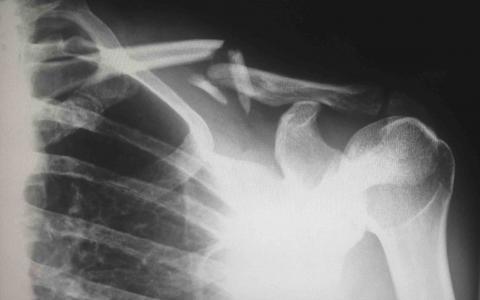

Direct force is the most typical cause of neck injuries. Since the neck is the main source of support for your skull, the neck can be easily injured by sudden head movements, overuse, and direct blows to the head or shoulder area. People who have been involved in a car accident usually suffer some sort of neck injury because they start in a still, non-moving position before their head is suddenly jolted forward or backward in a crash.

(image courtesy of Harlie Raethel)